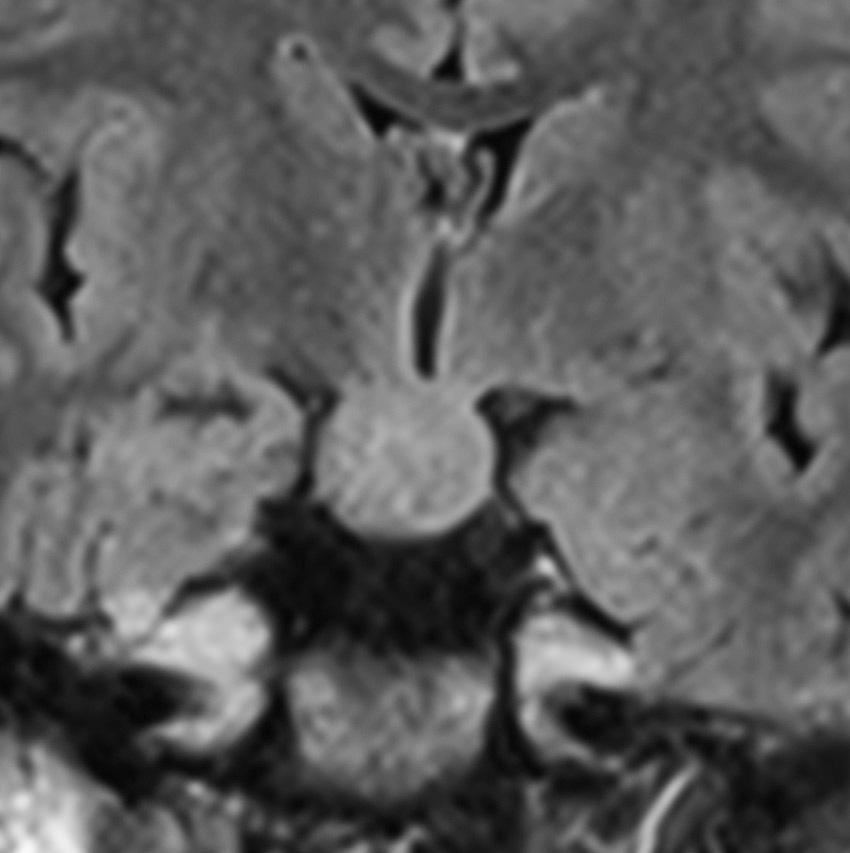

2歳でgelastic seizureを発症,6歳で思春期早発となりました

左視床下部に限局して柄を有するものです,左視索と乳頭体との境界はありません

おそらく左視床下部の機能低下と難治性の発作が原因で,左大脳半球の萎縮(あるいは発達不良)が認められます

予後がかなり不良だと判断して,2004年に摘出術をしました

術後のMRIです,pterional approach でしか摘出できない腫瘍でした

高い位置がとどかず少し取り残しました

gelastic seizureは減荷されましたが残り,術後に視野欠損を後遺しました

2019年時点でもこのよう過誤腫を治療することは困難です